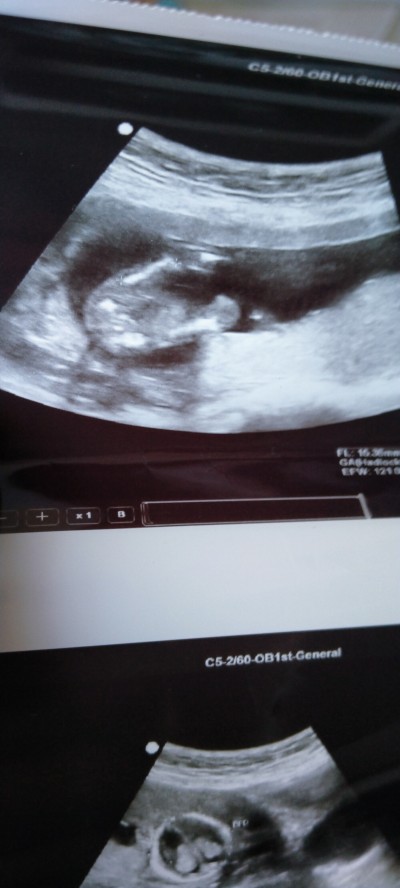

Doktordan iyi bilecek degilim ama bnmkinde erkek daha farkli ve net cikmis

Yada acisi farkli gobeginin ustune denk gelmis oda olabilir, oyle ise bir beyaz alan goruyorum, ama bence esya alacaksan unisex renkler al. Cok net gelmedi bana.diger kontrolu bekleyip emin olun derim

Bende göbeğinin üstünde gördüm biraz yukarda bellide olmuyor pek emin olamadım erkek dedi ama